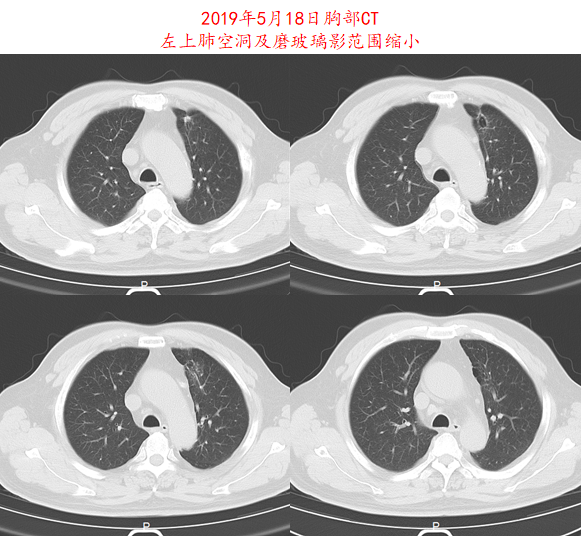

2019年4月16日开始给予信迪利单抗(200mg,q3w)+阿帕替尼(250mg,qd)治疗,治疗1周期后,患者症状明显改善,2周期后复查CT,疗效评价为部分缓解(PR;图3-4)。治疗期间患者出现1-2级皮疹,未观察到其他副作用。

image004.png

图3.患者2019年5月18日头部CT影像资料

image005.png

image006.png

图4.患者2019年5月18日胸部CT影像资料